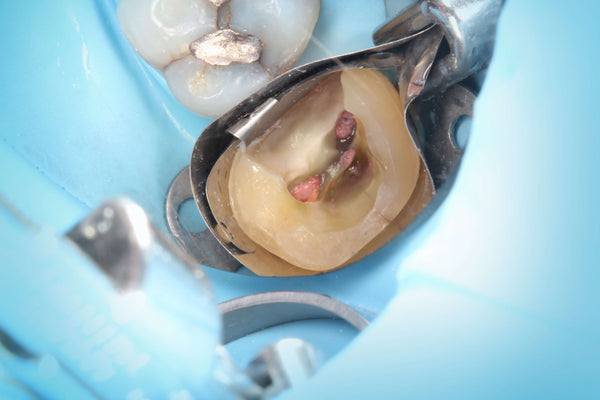

Direct Pulp Cap by Dr. Ahmad Fayad

Posted on May 15 2019

Noteworthy use of the Greater Curve technique by Dr. Ahmad Fayad. Introduction: 28 year old female with senstive Upper left first molar #26. No spontaneous pain, no lingering pain, no... Read More